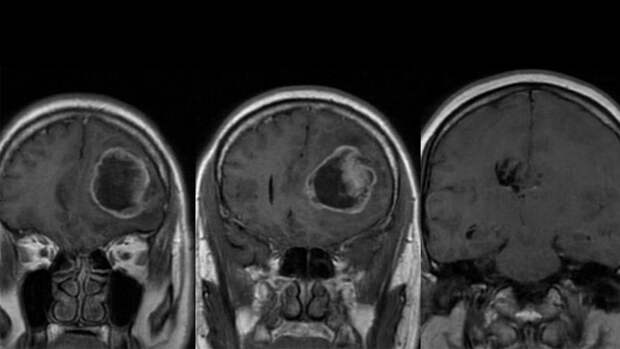

Мультиформная глиобластoма - наиболее злокачественная первичная опухоль головного мозга, на которую приходится до 52% первичных опухолей мозга и до 20% всех внутричерепных опухолей. Она способна привести к гибели пациента в течение двух лет даже при необходимом лечении, а без него - в течение трех месяцев. Поэтому важно выявить заболевание как можно раньше, еще до появления внешних признаков.